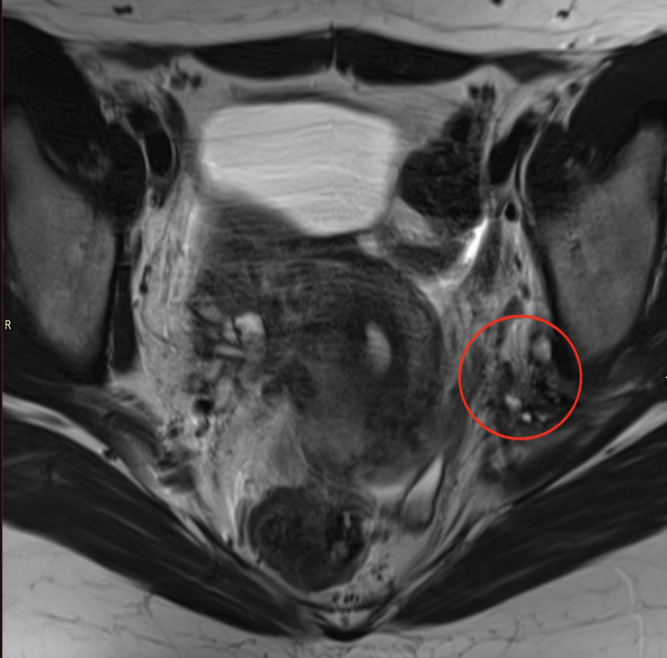

Extrapelvic Endometriosis Involving Pudendal and Sciatic Nerve Causing Obturator Muscle Atrophy.

Teaching point: Extrapelvic endometriosis involving pudendal and sciatic nerve may be a cause of lower limb pain.